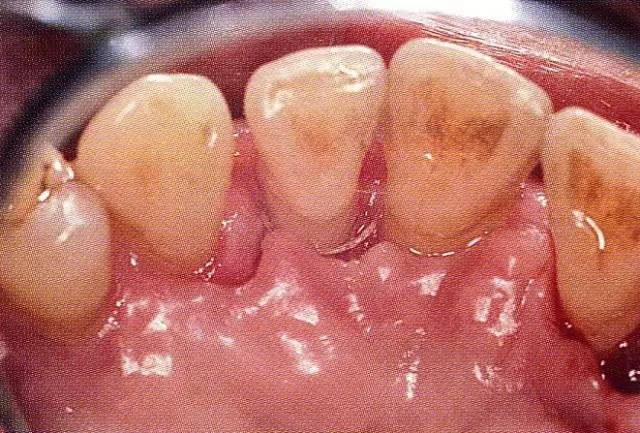

▲圖9-1  58歲,女性。右上2的上頜顎側(cè)可觀察到較大的3壁性骨缺損,術(shù)前牙周探診值時10mm。